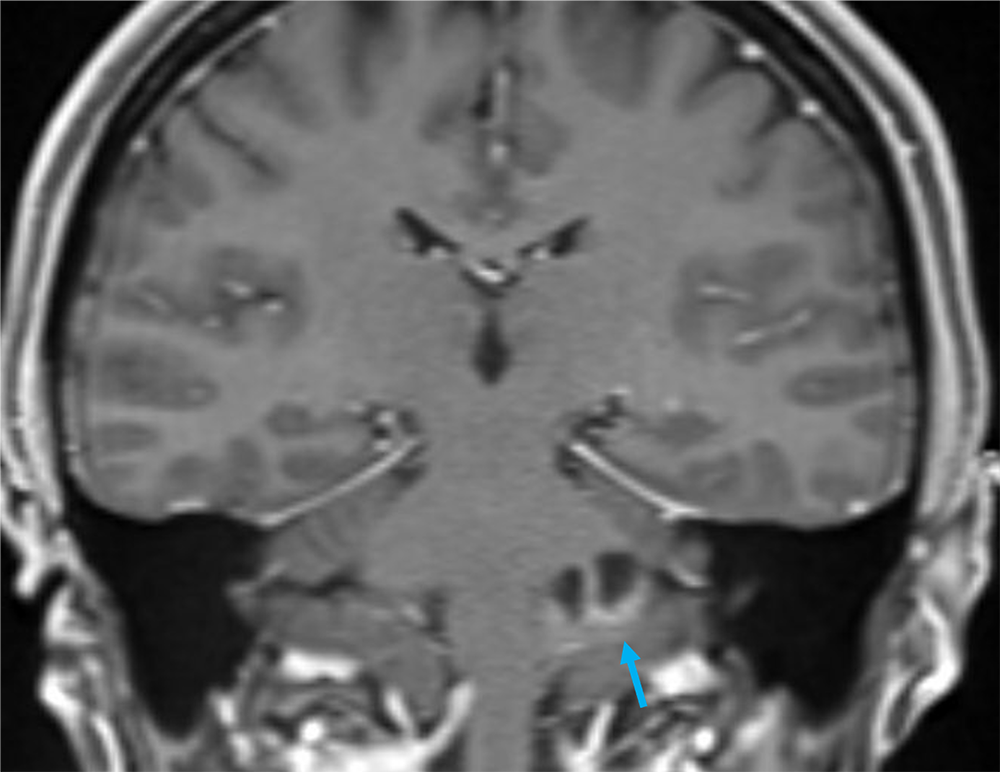

2か月前から頭重感および嘔気が持続しており、他院の単純CTにて左小脳腫瘍が疑われた。当院紹介となり、造影MRIが撮影された。

本症例では左小脳延髄角部に嚢胞成分を伴う腫瘍が存在し、左下位脳神経からの発生、もしくは小脳実質内腫瘍の鑑別が重要であった。前者であれば神経鞘腫、後者であればpilocytic astrocytomaの可能性が高くなる。3Dの脂肪抑制T1強調画像を撮影し、小脳実質内の可能性が高く、pilocytic astrocytomaを上位に考えた。手術が施行され、無事に完全摘出され上記の診断となった。

当該疾患の診断における造影MRIの役割

小脳腫瘍の鑑別において、造影MRIは必須である。本症例のように若年者の小脳実質内腫瘍の場合、特に血管芽腫との区別が重要となる。血管芽腫も嚢胞成分を伴う腫瘤を呈することが多いが、充実成分は強い造影効果を呈する。本症例は血管芽腫を疑うような強い造影効果とは言えず、pilocytic astrocytomaを疑うことが可能であった。